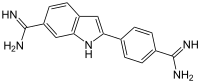

| IUPAC name

2-(4-Amidinophenyl)-1H-indole-6-carboxamidine | |

| Other names

4′,6-Diamidino-2-phenylindole | |

| C16H15N5 | |

| Molar mass | 277.331 g·mol−1 |